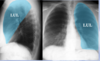

* Right pleural effusion * Notice the loss of the costophrenic angle

83

What is this CXR showing?

* RML pneumonia * You can rule out RLL pneumonia because there is no accumulation at the base of the lung. * A lateral CXR will have the best view for confirmation.